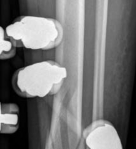

Removal of implants is not mandatory but recommended if implants are prominent under the subcutaneous envelope of the distal tibia. Implant removal should be undertaken only after healing is complete, ie, after 1 year at the earliest. This patient had achieved good radiographic and functional healing at the 1-year postoperative review (Fig 2.2-8 and Fig 2.2-9).

Fig 2.2-8a–b Postoperative x-rays at 1 year showing healed fractures, implants in situ, and limited tibiotalar arthrosis.

1. AP view.

2. Lateral view.